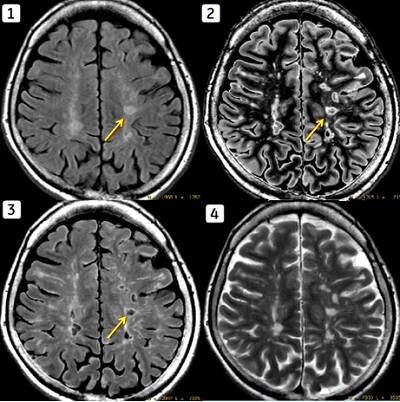

The figure below illustrates an example of a lesion, as visualized on a conventional T2 FLAIR image and multiple calculated MAGiC series. Note the similar performance of DIR to conventional FLAIR.

Figure 3. Anatomy and lesion visualization on conventional T2 FLAIR vs. multiple calculated MAGiC series

Table 3. Image legend

NumberDescription

1Conventional T2 FLAIR

2MAGiC DIR

3MAGiC T2 FLAIR

4MAGiC T2